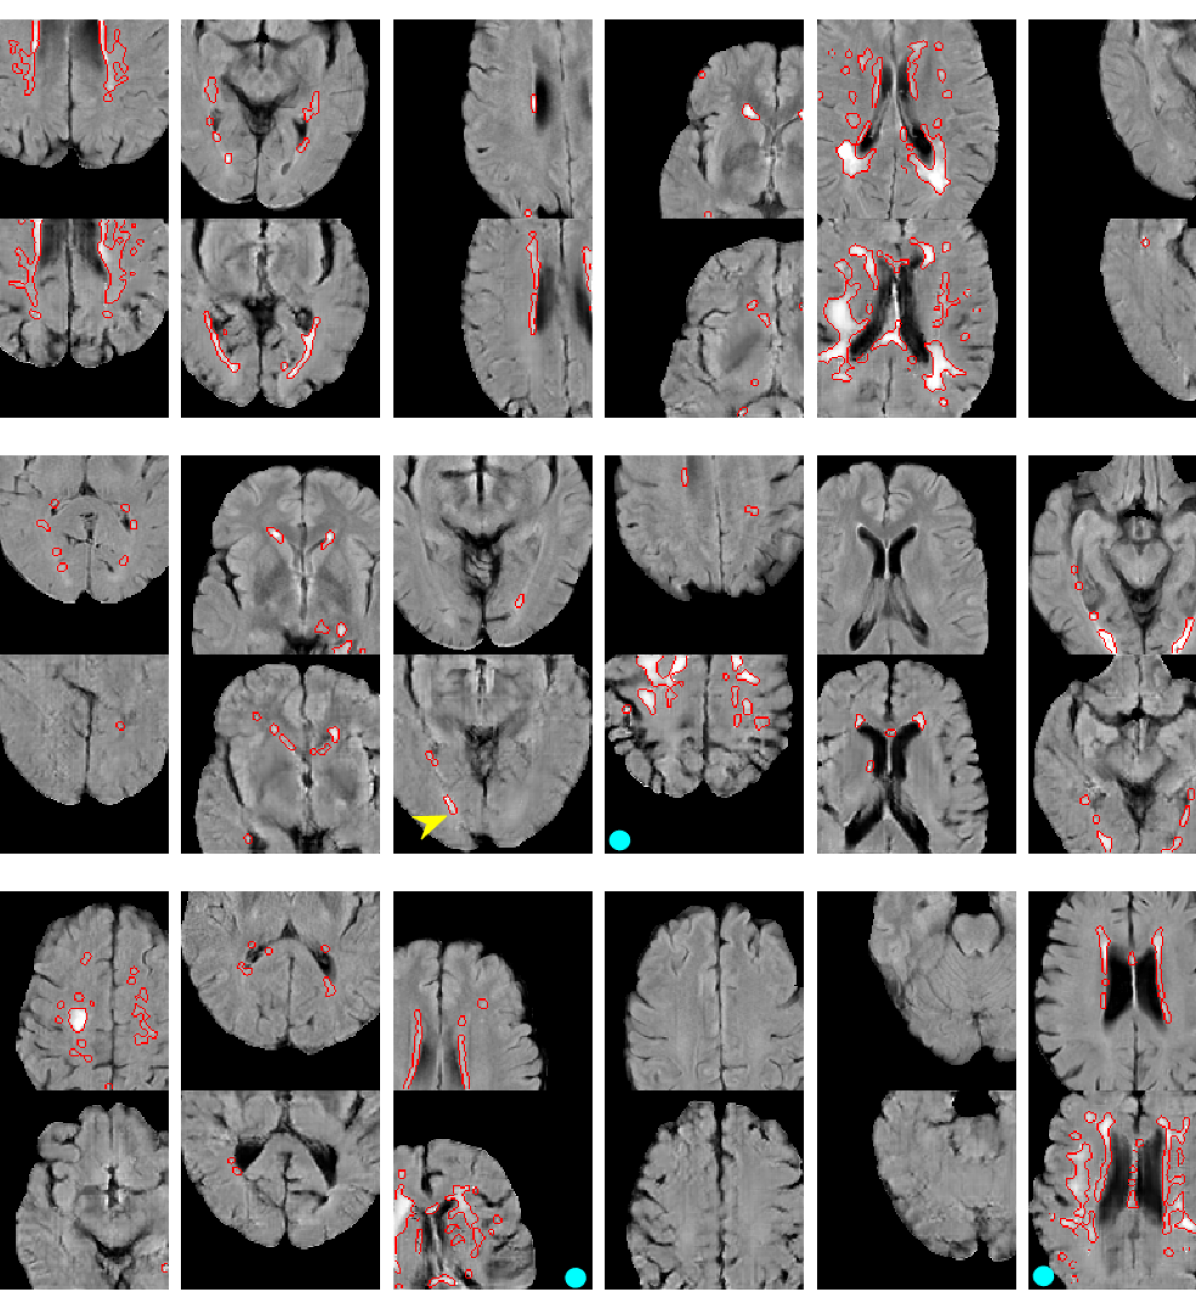

Figure 1: Examples of real and GAN generated synthetic patches. Left CSF. Red: Cortical CSF. Green: Brain stem CSF. Blue: Ventricular CSF. Right: WMH.

Table 1 summarises the five sets of experiments which were carried out to answer the questions posed earlier. In each experiment, the segmentation network is treated as a black box and unchanged. This provides a fair platform upon which to observe the effects of GAN augmentation by ensuring that any changes in performance are as a result of the additional synthetic data, and not of changes in the network itself. GAN training took 36 hours, each UNet took 4 hours, each Res-UNet took 24 hours and each DeepMedic network took 24 hours on an Nvidia GTX 1080 Ti or similar GPU. All segmentation experiments on CT were repeated 8 times, while those on MR were repeated 14 times to compensate for a higher observed variance. Examples of real and synthetic patches generated for each dataset can be seen in Figure 1.

As well as the quantitative segmentation results, the generated MR images were also compared to their nearest neighbour in the training set to elucidate what extra information GAN augmentation provides. These images, a subset of which are shown in Figure 3, were examined looking for cases where: lesions were duplicated on different anatomy; lesions were changed whilst anatomy stays the same; the nearest neighbour is substantially different. The latter indicates the GAN has learned a smooth manifold leading to potentially novel anatomy.

Figure 3: Synthetic images (top of pair) with their nearest neighbours in the training set (bottom of pair) from GANs trained on patches from 5, 25 and 50 real MR images. Some local signs of successful augmentation are indicated using green (same lesions, different anatomy) and yellow (same anatomy, different lesions) arrows, and novel images (new anatomy and lesions) are shown with blue dots.

Figure 3 provides an interesting insight into what additional information is being provided by GAN augmentation. In the case of 5 training images, it is clear that each generated image is based heavily on an image from the training set. This is unsurprising as there are very few images to train on, and little variation which can be learned. However, there are subtle differences present in the majority of synthetic images. There are cases where lesions present in the real image are not reproduced in the synthetic image, as well as cases where the shape and number of lesions present in the synthetic image differ from those in the real image. Both of these effects can be extremely valuable to prevent overfitting when training a model - the former decoupling the presence of lesions from the surrounding anatomy, and the latter providing more variety of pathology. When the number of training images increases to 25, we begin to see cases where there are no close matches in the training set, in addition to the cases of differing anatomy and pathology seen previously. This trend gets even stronger in Figure 3 where all 50 training images are used. There are often substantial differences between the synthetic images and their closest real image, suggesting that the GAN has learned to produce data substantially beyond what was provided to it. We also observe that these modifications appear reasonable in all cases, with no obvious unrealistic lesions or anatomy being synthesised.